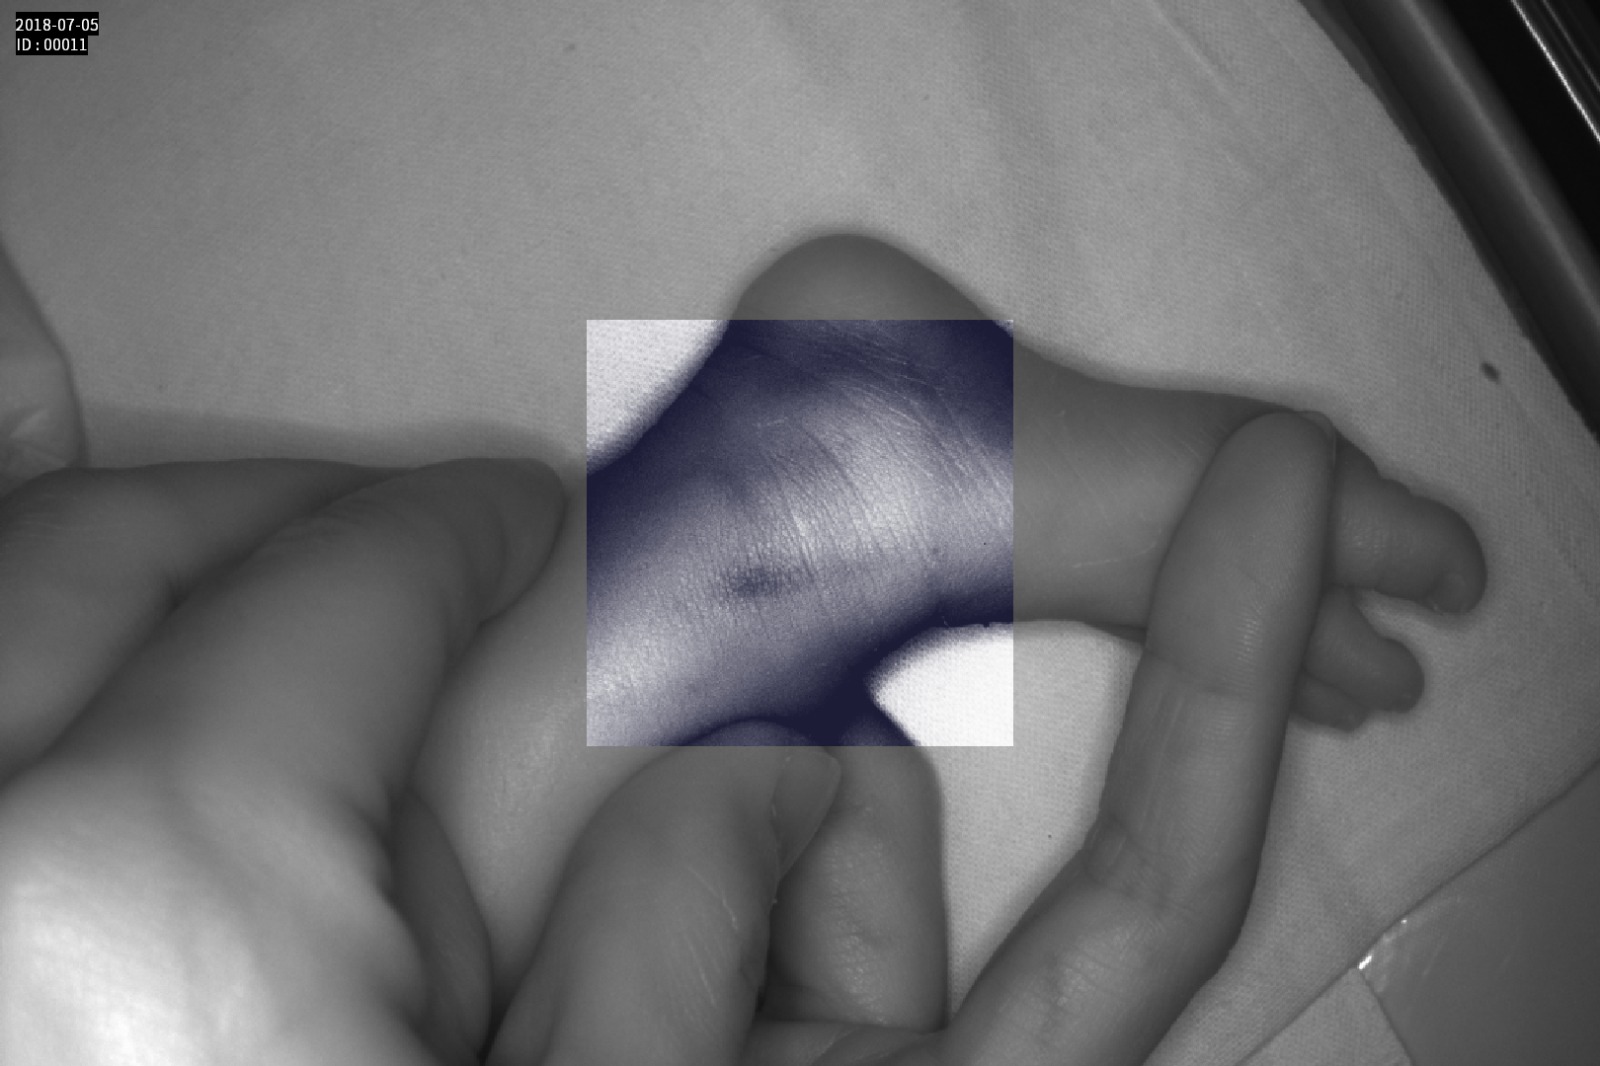

Dispozitiv medical portabil, non-contact, ce ajută la vizualizarea venelor pentru efectuarea puncției venoase, intervențiilor chirurgicale plastice, diagnosticul venelor varicoase.

Grad mare de detecție a venelor greu vizibile până la 10 mm adâncime (inclusiv vene faciale)

Imaginea venelor este proiectată pe monitorul propriu în timp real si ajută la identificarea corectă și precisă

Multiple aplicații de vizualizare vene atât la sugari cât și la pacienții obezi sau în urgențe indiferent de tonul de culoare a pielii